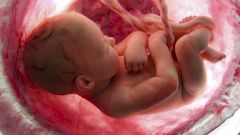

Все начинают свою жизнь в утробе матери, и это факт. Вы не поверите своим глазам, когда увидите эти невероятные моменты развития человеческого плода: от самого зачатия и до родов.